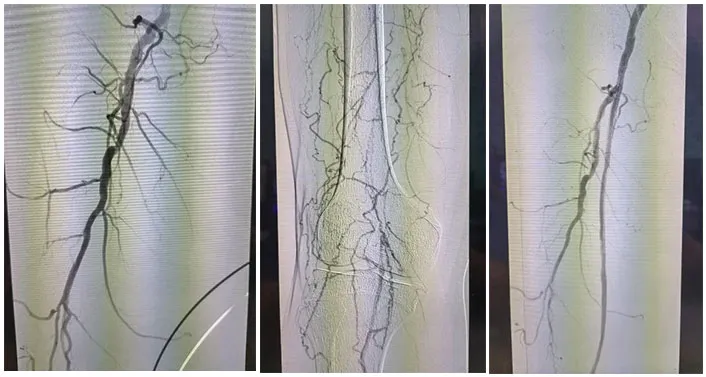

术å‰è¯Šæ–­åQšå¤–院CTA½CÞZ¸‹è‚¢åŠ¨è„‰ç¡¬åŒ–é—­å¡žç—‡,åŒä¾§è†ä¸‹åŠ¨è„‰å¤šå‘多支下肢动脉闭塞ã€?/p>

手术˜q‡ç¨‹åQ?/strong>å¯ég¸å¯¼ç®¡é…åˆå»ºç«‹é€šèµ\åŽï¼Œä½¿ç”¨2.5*150mmã€?*120mmçƒå›Šæ‰©å¼ èƒ«åŽåŠ¨è„‰ç‹­çª„ŒDµï¼Œä½¿ç”¨2*80mmã€?.5*150mmçƒå›Šæ‰©å¼ è…“动脉狭½H„段åQŒé¢„扩åŽä½¿ç”¨¾U¦æŸåž‹è¯ç‰©çƒå›?*120mmã€?*150mm分别扩张胫åŽåŠ¨è„‰ã€è…“åŠ¨è„‰ã€‚å¤æŸ¥é€ åª„½Cºå†…膜光滑,无造媄剂外渗,è†ä¸‹˜qœç«¯åŠ¨è„‰ä¸¤æ”¯æ˜‘Öª„è‰¯å¥½ã€‚æ‰‹æœ¯é¡ºåˆ©ï¼Œæœ¯åŽæ‚£è€…安˜q”ç—…æˆÑ€?/p>

主诉åQ?/strong>åŒä¸‹è‚¢åŠ¨è„‰é—­å¡?月余åQŒå·¦ä¸‹è‚¢æœ¯åŽ3周余ã€?/p>

术å‰è¯Šæ–­åQ?/strong>下肢CTA½CºåŒä¸‹è‚¢åŠ¨è„‰å¤šå‘æ··åˆæ–‘å—åQŒç®¡è…”轻中度狭窄åQŒå·¦ä¾§è‚¡æ·±åŠ¨è„‰å¤šå‘æØœåˆæ–‘å—,½Ž¡è…”局部闭塞ã€?/p>

手术˜q‡ç¨‹åQ?/strong>å¯ég¸å¯¼ç®¡é…åˆå»ºç«‹é€šèµ\åŽï¼Œä¿æŠ¤ä¼žä¸‹ä½¿ç”¨4*150mmçƒå›Šé¢„扩张病å˜ï¼Œåˆ†åˆ«äº¤æ¢5*200mm¾U¦æŸåž‹è¯ç‰©çƒå›Šæ‰©å¼ é—­å¡žæ®µåŠè‚¡‹¹…动脉上ŒD늋­½H„处åQ?*150mm¾U¦æŸåž‹è¯ç‰©çƒå›Šæ‰©å¼ èƒ«è…“干开å£ä¸ŠŒDµï¼Œéž˜å†…造媄昄¡¤ºè‚¡æµ…å¼€å£å¤„有残余狭½H„,余闭塞段完全å¤é€šï¼Œå†…膜光整åQŒè¡€‹¹é€šç•…åQŒå¼•å…¥DES6*40m支架一枚予以股‹¹…å¼€å£å¤„释放åQŒå¤æŸ¥é€ åª„æç¤ºç‹­çª„解除åQŒæœªè§é€ åª„剂外渗,è†ä¸‹˜qœç«¯åŠ¨è„‰å„分支显å½Þp‰¯å¥½ï¼Œæœªè§æ˜Žæ˜¾æ “å¡žã€‚æ‰‹æœ¯é¡ºåˆ©ï¼Œæœ¯åŽæ‚£è€…安˜q”ç—…æˆÑ€?/p>

以上病例åQŒæœ¯ä¸­å›¢é˜Ÿå‡é€šè¿‡¾U¦æŸåž‹è¯çƒæˆåŠŸå¼€é€šç—…å˜è¡€½Ž¡ï¼Œæœ¯åŽè¡€‹¹æ¢å¤è‰¯å¥½ï¼Œæ›²ä¹ä¸°æ•™æŽˆè¡¨½C?”¾U¦æŸåž‹è¯çƒé€šè¿‡â€˜ä»‹å…¥æ— æ¤å…¥â€™ç†å¿µï¼Œå®žçŽ°äº†â€˜ç²¾å‡†ç»™è¯â€™ä¸Žâ€˜ç‰©ç†æˆå½¢â€™çš„ååŒæ•ˆæžœåQŒå°¤å…‰™€‚åˆòq´è½»æ‚£è€…或支架¼›å¿Œç—‡äh¾Ÿ¤ï¼Œæ˜¯è¡€½Ž¡ä»‹å…¥æ²»ç–—çš„é‡è¦æŠ€æœ¯è¡¥å……ã€?#8221;